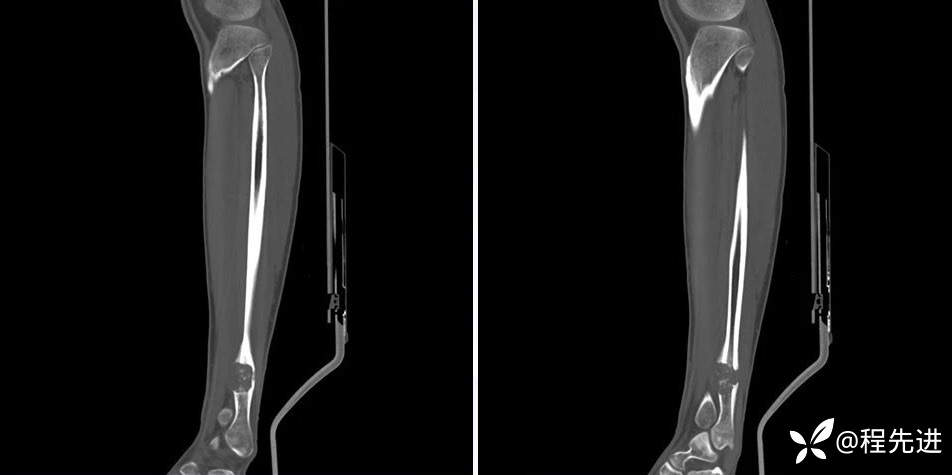

CT平扫

CT骨窗

CT平扫、增强动脉期、静脉期

平扫67HU、动脉期81HU、静脉期93HU